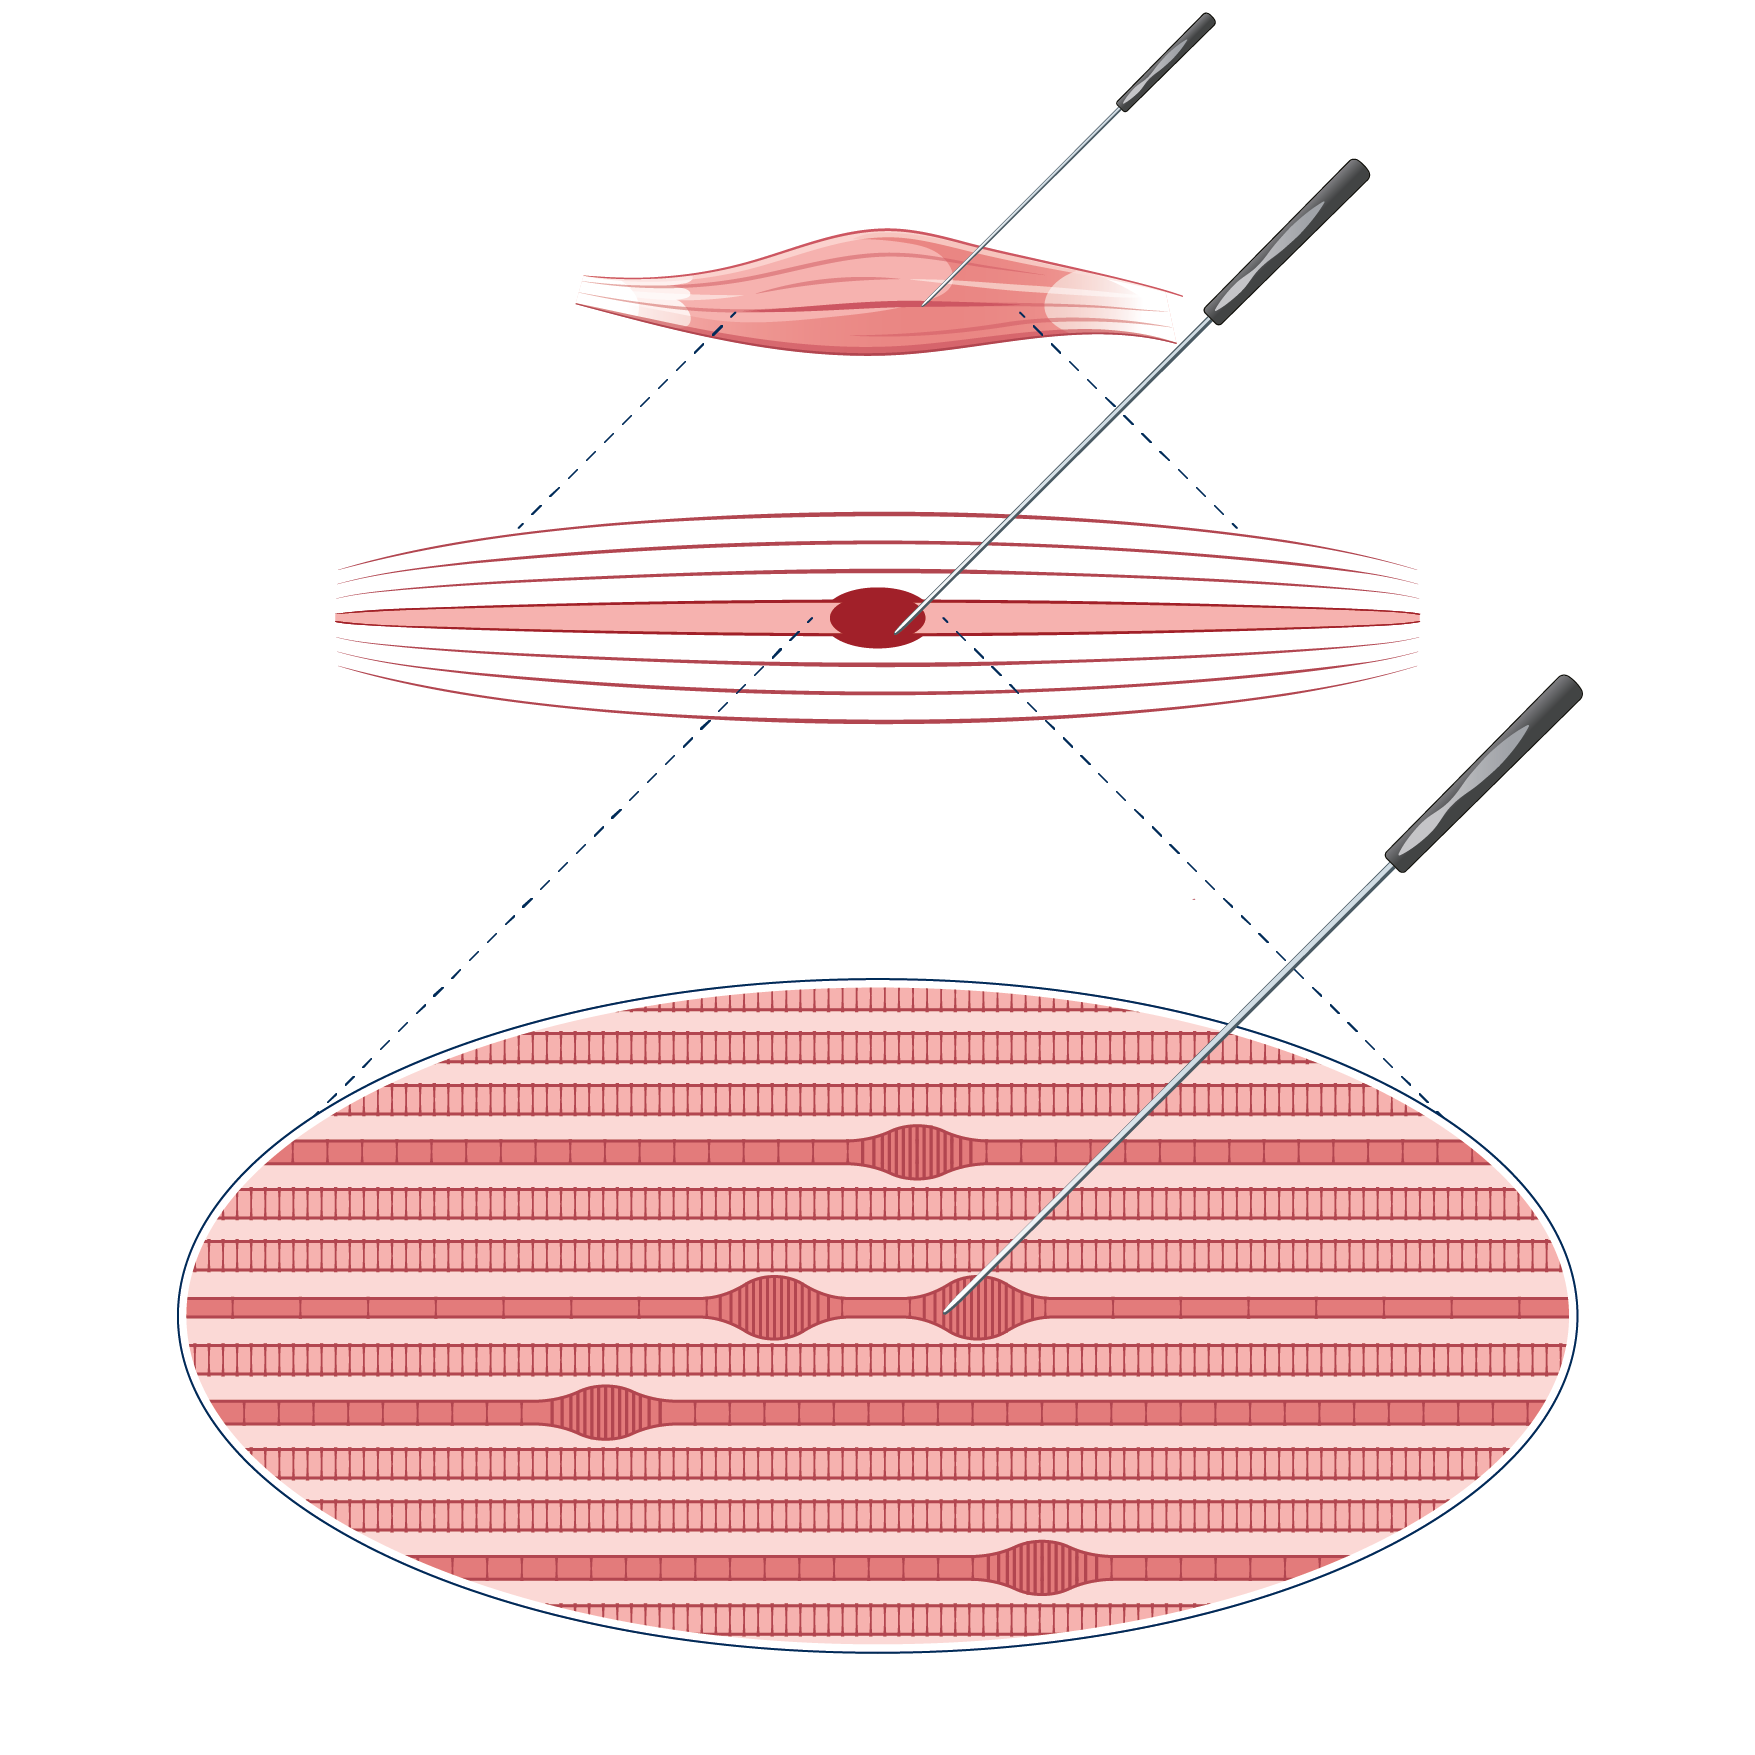

Wenn Triggerpunkte (chronische Überlastungszonen im Muskel und den Faszien) die Schmerzursache sind, gelingt eine Heilung häufig mittels einer gezielten Behandlung des Muskels mit Nadeln (Dry Needling) oder mit Triggerpunktinfiltrationen (auch Wet Needling genannt).

Triggerpunkte

Muskuläre Triggerpunkte sind anhaltende Kontraktionen von einigen/wenigen Muskelfasern eines Muskels. Diese entstehen häufig als Reaktion einer chronischen Überlastung von Muskeln oder auch durch eine direkte oder indirekte Krafteinwirkung. Ein typisches Beispiel für eine muskuläre Überlastungssituation ist eine ungünstige Haltung am Computer – zum Beispiel beim Surfen auf einer Praxis-Homepage. Ein häufiger Mechanismus für die unfallbedingte Entstehung von Triggerpunkten ist die Überdehnung von Nackenmuskeln bei einem Schleudertrauma.

Triggerpunkte können – je nachdem wie stark ein Muskel befallen ist – mit einem schmerzfreien Zustand vereinbar sein oder aber auch die Ursache für einen invalidisierenden/immobilisierenden Schmerzzustand sein. Forschungsresultate zeigen, dass sich in Triggerpunkten ein übersäuertes Milieu mit sehr tiefen Sauerstoffwerten befindet. Ohne Sauerstoff fehlt auch der biochemische Energielieferant ATP (Adenosintriphosphat), welchen es für das Lösen der zusammengezogenen Muskelfasern braucht.

Triggerpunktinfiltrationen und Dry Needling als Behandlungsmöglichkeit

In den 40er-Jahren entdeckten Mediziner, dass die Infiltration von Lokalanästhesie in die Triggerpunkte zu einer anhaltenden Schmerzfreiheit führen kann. Im weiteren Verlauf entdeckten die Forscher, dass ein ähnlicher Effekt auch bei der Infiltration von Kochsalzlösung zu beobachten war. Als erforscht war, dass eine ähnliche Wirkung auch durch alleinige Nadelstiche in die Triggerpunkte (ohne Infiltration einer Flüssigkeit) auftrat, war das Dry Needling geboren: Triggerpunkte lassen sich also durch Nadelstiche in den Muskel (Dry Needling) auflösen.

Man geht davon aus, dass Nadelstiche die Durchblutung und somit die Sauerstoffversorgung in den Triggerpunkten ankurbeln, woraufhin sich die zusammengezogenen Muskelfasern – und damit auch die Triggerpunkte – lösen.